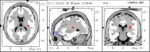

The first and most important step in treating concussions is a proper diagnosis. A traumatic brain injury (TBI) or Concussion impacts the brain in many ways. It takes weeks to months to fully recover from a concussion. But it often takes years for post concussive symptoms to appear with some cognitive losses becoming long-term.